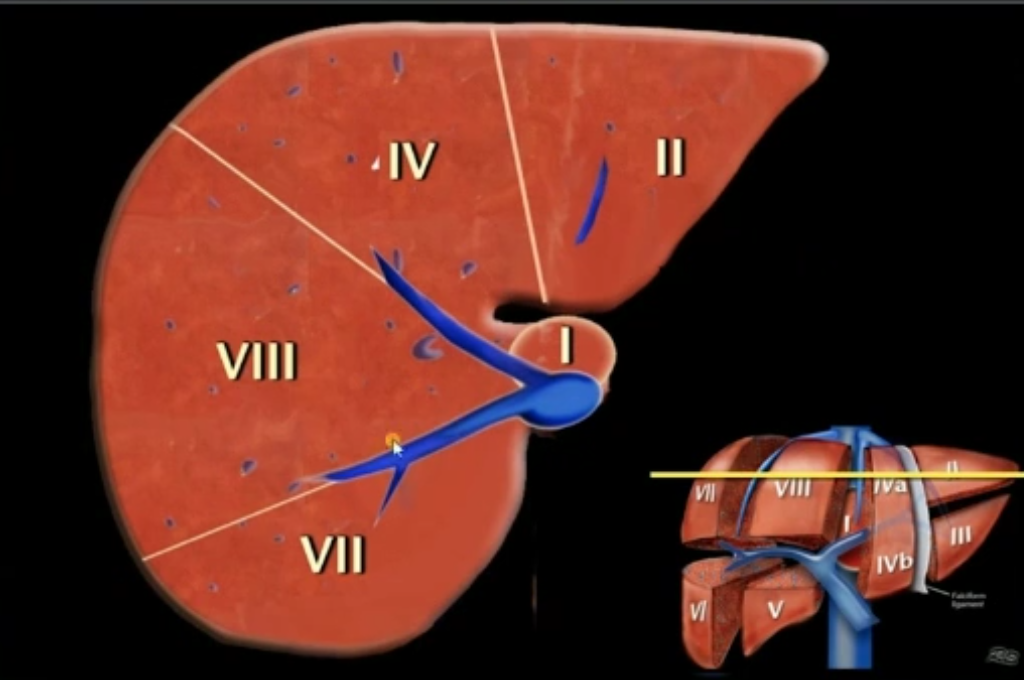

bismuth分段

- 纵向中肝静脉分左右,右肝静脉分右前后,镰状韧带分左内外

- 从右到左:右肝后(右肝静脉)右肝前(中肝静脉)左肝内(镰状韧带)左肝外

- 纵向门静脉左右支分上下两份

中心1,其他顺时针标号

解剖标记

- 第一肝门上方中肝静脉,右肝静脉

- 门静脉左支分左肝上下

- 门静脉右支分右肝上下

- 顺时针在片子里是左到右